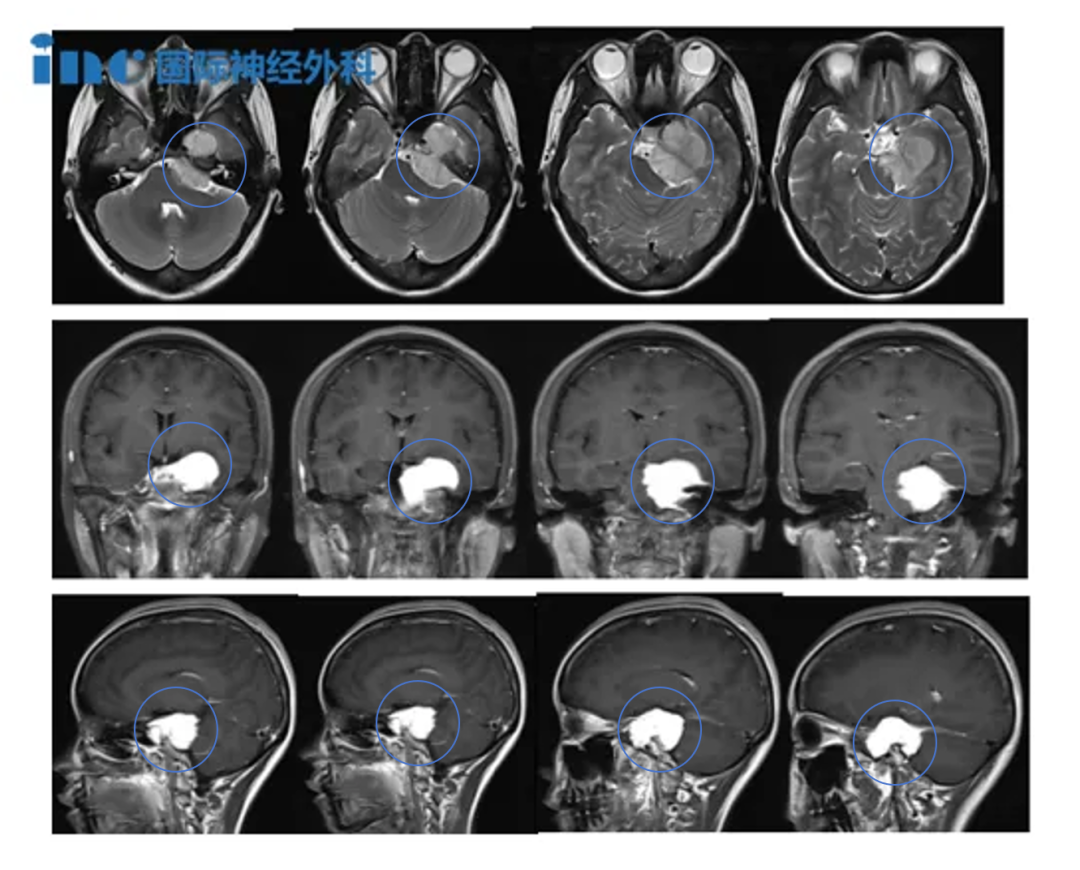

但当我将这个消息告诉家人后,他们都认为无论肿瘤是否良性,长在脑子里就像个定时炸弹,必须处理。在他们的建议下,我开始咨询多位专家。这时我才知道肿瘤已经很大了(45x38x32mm),所有医生都建议尽快手术,我才意识到问题的严重性。

▼岩斜区脑膜瘤,随着肿瘤大小增大及脑干水肿机率增加,手术难度逐渐增加